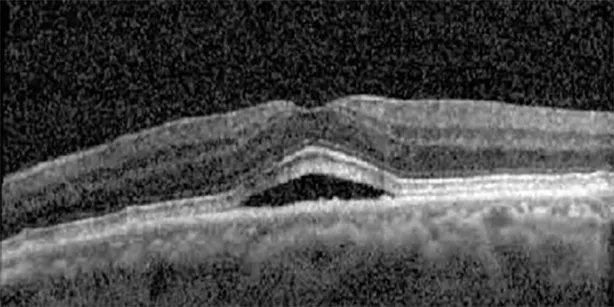

The patient began treatment with oral pemigatinib daily and was followed up for an ophthalmic examination during the second treatment cycle approximately 5 weeks into the treatment process. The patient had at this stage received 28 doses of 13.5 mg per day, which was administered in cycles of 14 on-days and 7 off-days, and had no visual or ophthalmic complaints. The non-corrected VA was OD 20/30 + 1 and OS 20/20. The OCT examinations revealed subfoveal SRF bilaterally. The fundus examination was otherwise unremarkable outside the patient’s prior documented peripheral drusen. Repeat autofluorescence was overall unchanged, though a slight hypofluorescent ring may be visualized in Figure 2. The current pemigatinib protocol recommendation for asymptomatic patients suggests no dose modification; however, with worsening presentation or positive symptoms, it is recommended to withhold pemigatinib. After discussion with the patient’s oncologist, it was decided to continue the medication at this time. Serial monitoring of the patient’s symptoms, vision, and SRF were conducted on specific days during active treatment cycles and days off-cycle to monitor the SRF. Subsequent evaluations demonstrated complete resolution of SRF while off-cycle, and asymptomatic re-accumulation of fluid while on-cycle with varying levels of VA. (Table 1) As we see demonstrated in the table below, in the later stages of the active cycles, such as day 13 of 14 of cycle 2, day 13 of 14 of cycle 3, day 13 of 14 of cycle 4, and day 14 of 14 on cycle 5, the patient’s VA showed no correlative changes based on the presence of SRF. The fluctuations in the patient’s VA certainly occurred, but were likely to be secondary to surface changes, as certain off-cycle days actually presented with lower acuities than days when the SRF was present on OCT examination.

Highlights the visual acuity, central macular thickness, and the physical OCT of the macula for this patient in both the right and left eyes during various stages of the patient's chemotherapy treatment cycle.